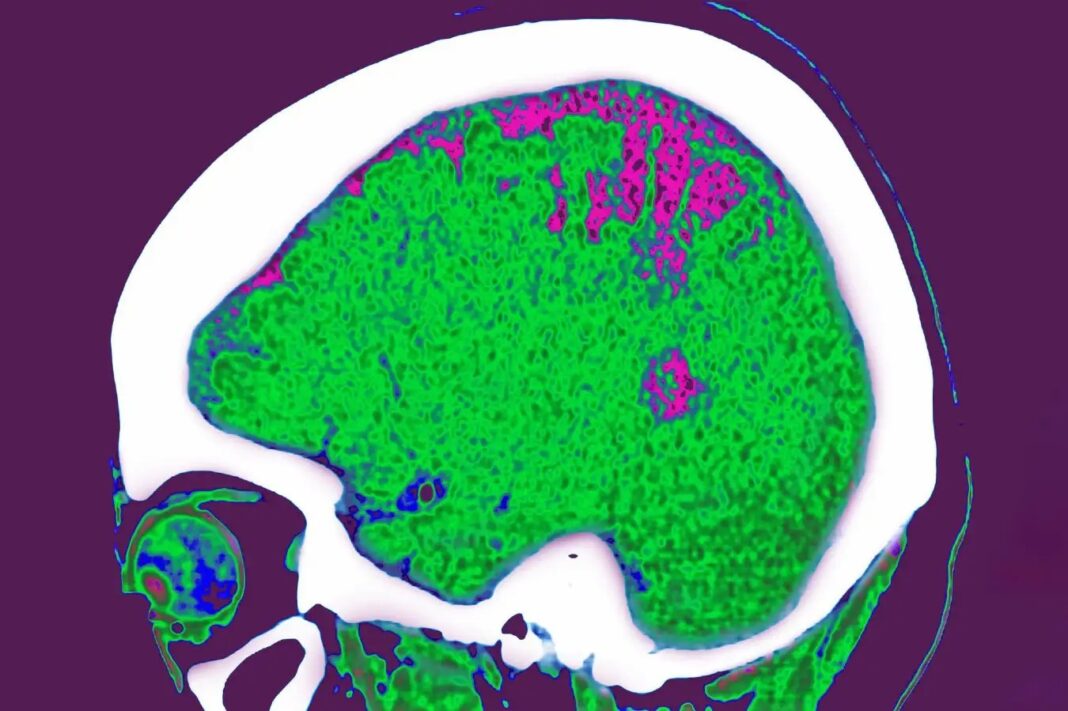

Останні дослідження дійсно шокують своєю точністю: Виявляється, жир на руках, ногах, тулуба і навіть навколо внутрішніх органів (вісцеральний жир)різний вплив на мозок. І це не просто кореляція, а, можливо, причинно -наслідкові стосунки.

- Жир на руках і на тулубі: Він пов’язаний з витонченням сенсомоторної кори (область, що відповідає за рух) та зменшенням об’єму гіпокампу – критично важливим для пам’яті області, яка є одним із перших, на які впливає хвороба Альцгеймера. Цей факт особливо тривожний і підкреслює важливість підтримки м’язової маси та активності, щоб мінімізувати вплив жиру на ці ділянки.

- Жир на ногах: Він пов’язаний зі зменшенням узгодженості лімбічної мережі мозку, яка регулює емоції та обробку винагороди. Це може пояснити, чому люди з надмірним жиром на ногах можуть відчувати емоційну нестабільність або труднощі з мотивацією.

- Вісцеральний жир: Найсильніший зв’язок із зміненою функцією мозку, включаючи погіршення білої речовини – структуру, яка передає сигнали між ділянками мозку. Це особливо небезпечно, оскільки біла речовина відіграє ключову роль у когнітивних процесах.